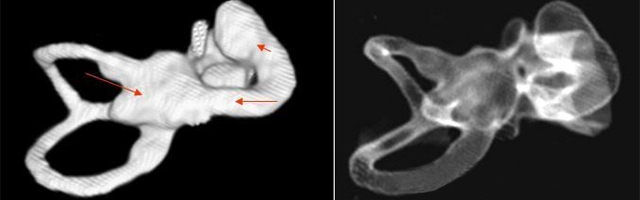

雙側內耳畸形:左側無內耳迷路及內耳道機構,為米歇爾畸形;右側空耳蝸及前庭擴大,為先天性耳蝸畸形

先天性耳蝸畸形伴前庭和外半規管發育不良